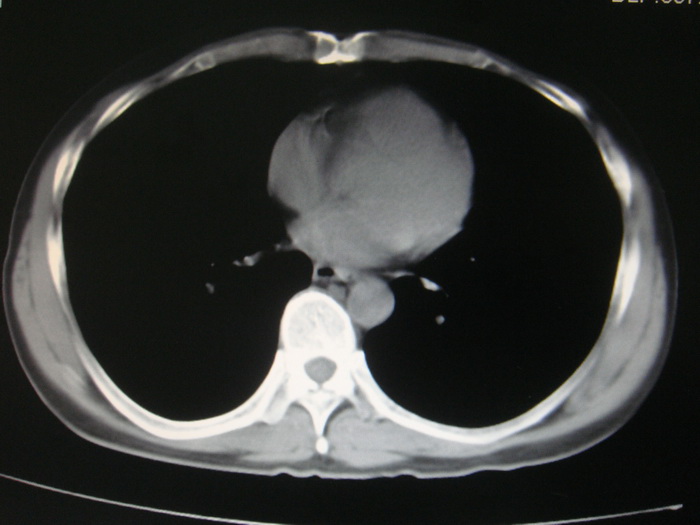

标题: CT28366:男性,45岁,偶尔发现右颈部肿块行胸部CT扫描。 [打印本页]

男性,45岁,偶尔发现右颈部肿块行胸部ct扫描。

两肺多发结节灶及纵膈淋巴结肿大考虑为转移

两肺多发性转移瘤,纵隔淋巴结转移。

两肺多发性转移瘤,纵隔淋巴结转移。食道中上段管壁似乎增厚,作相关检查。

两肺多发性转移瘤,前上纵隔淋巴结转移。